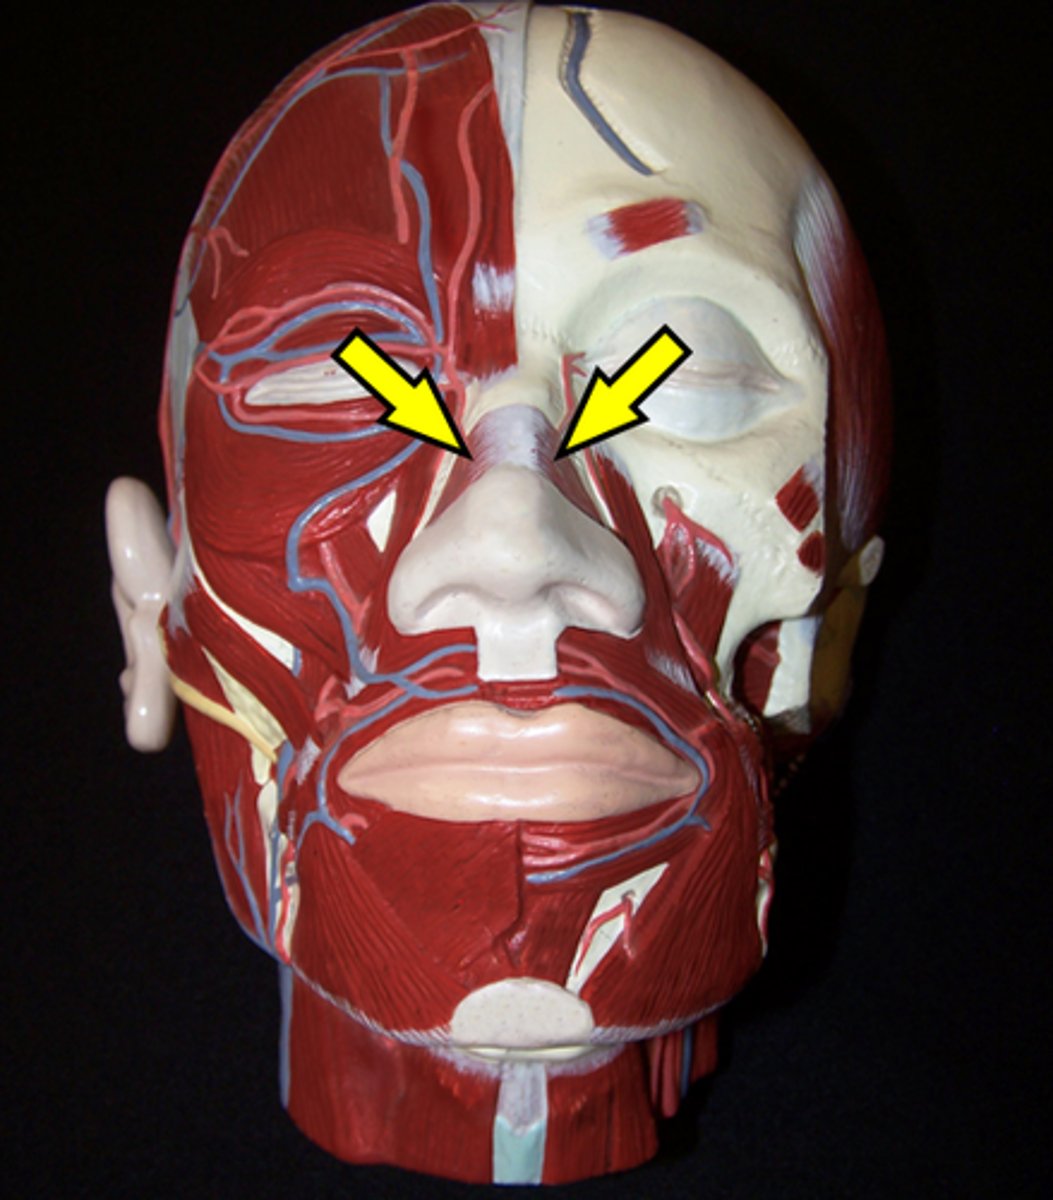

Corrugator Supercillii

Orbicularis Oculi

Procerus